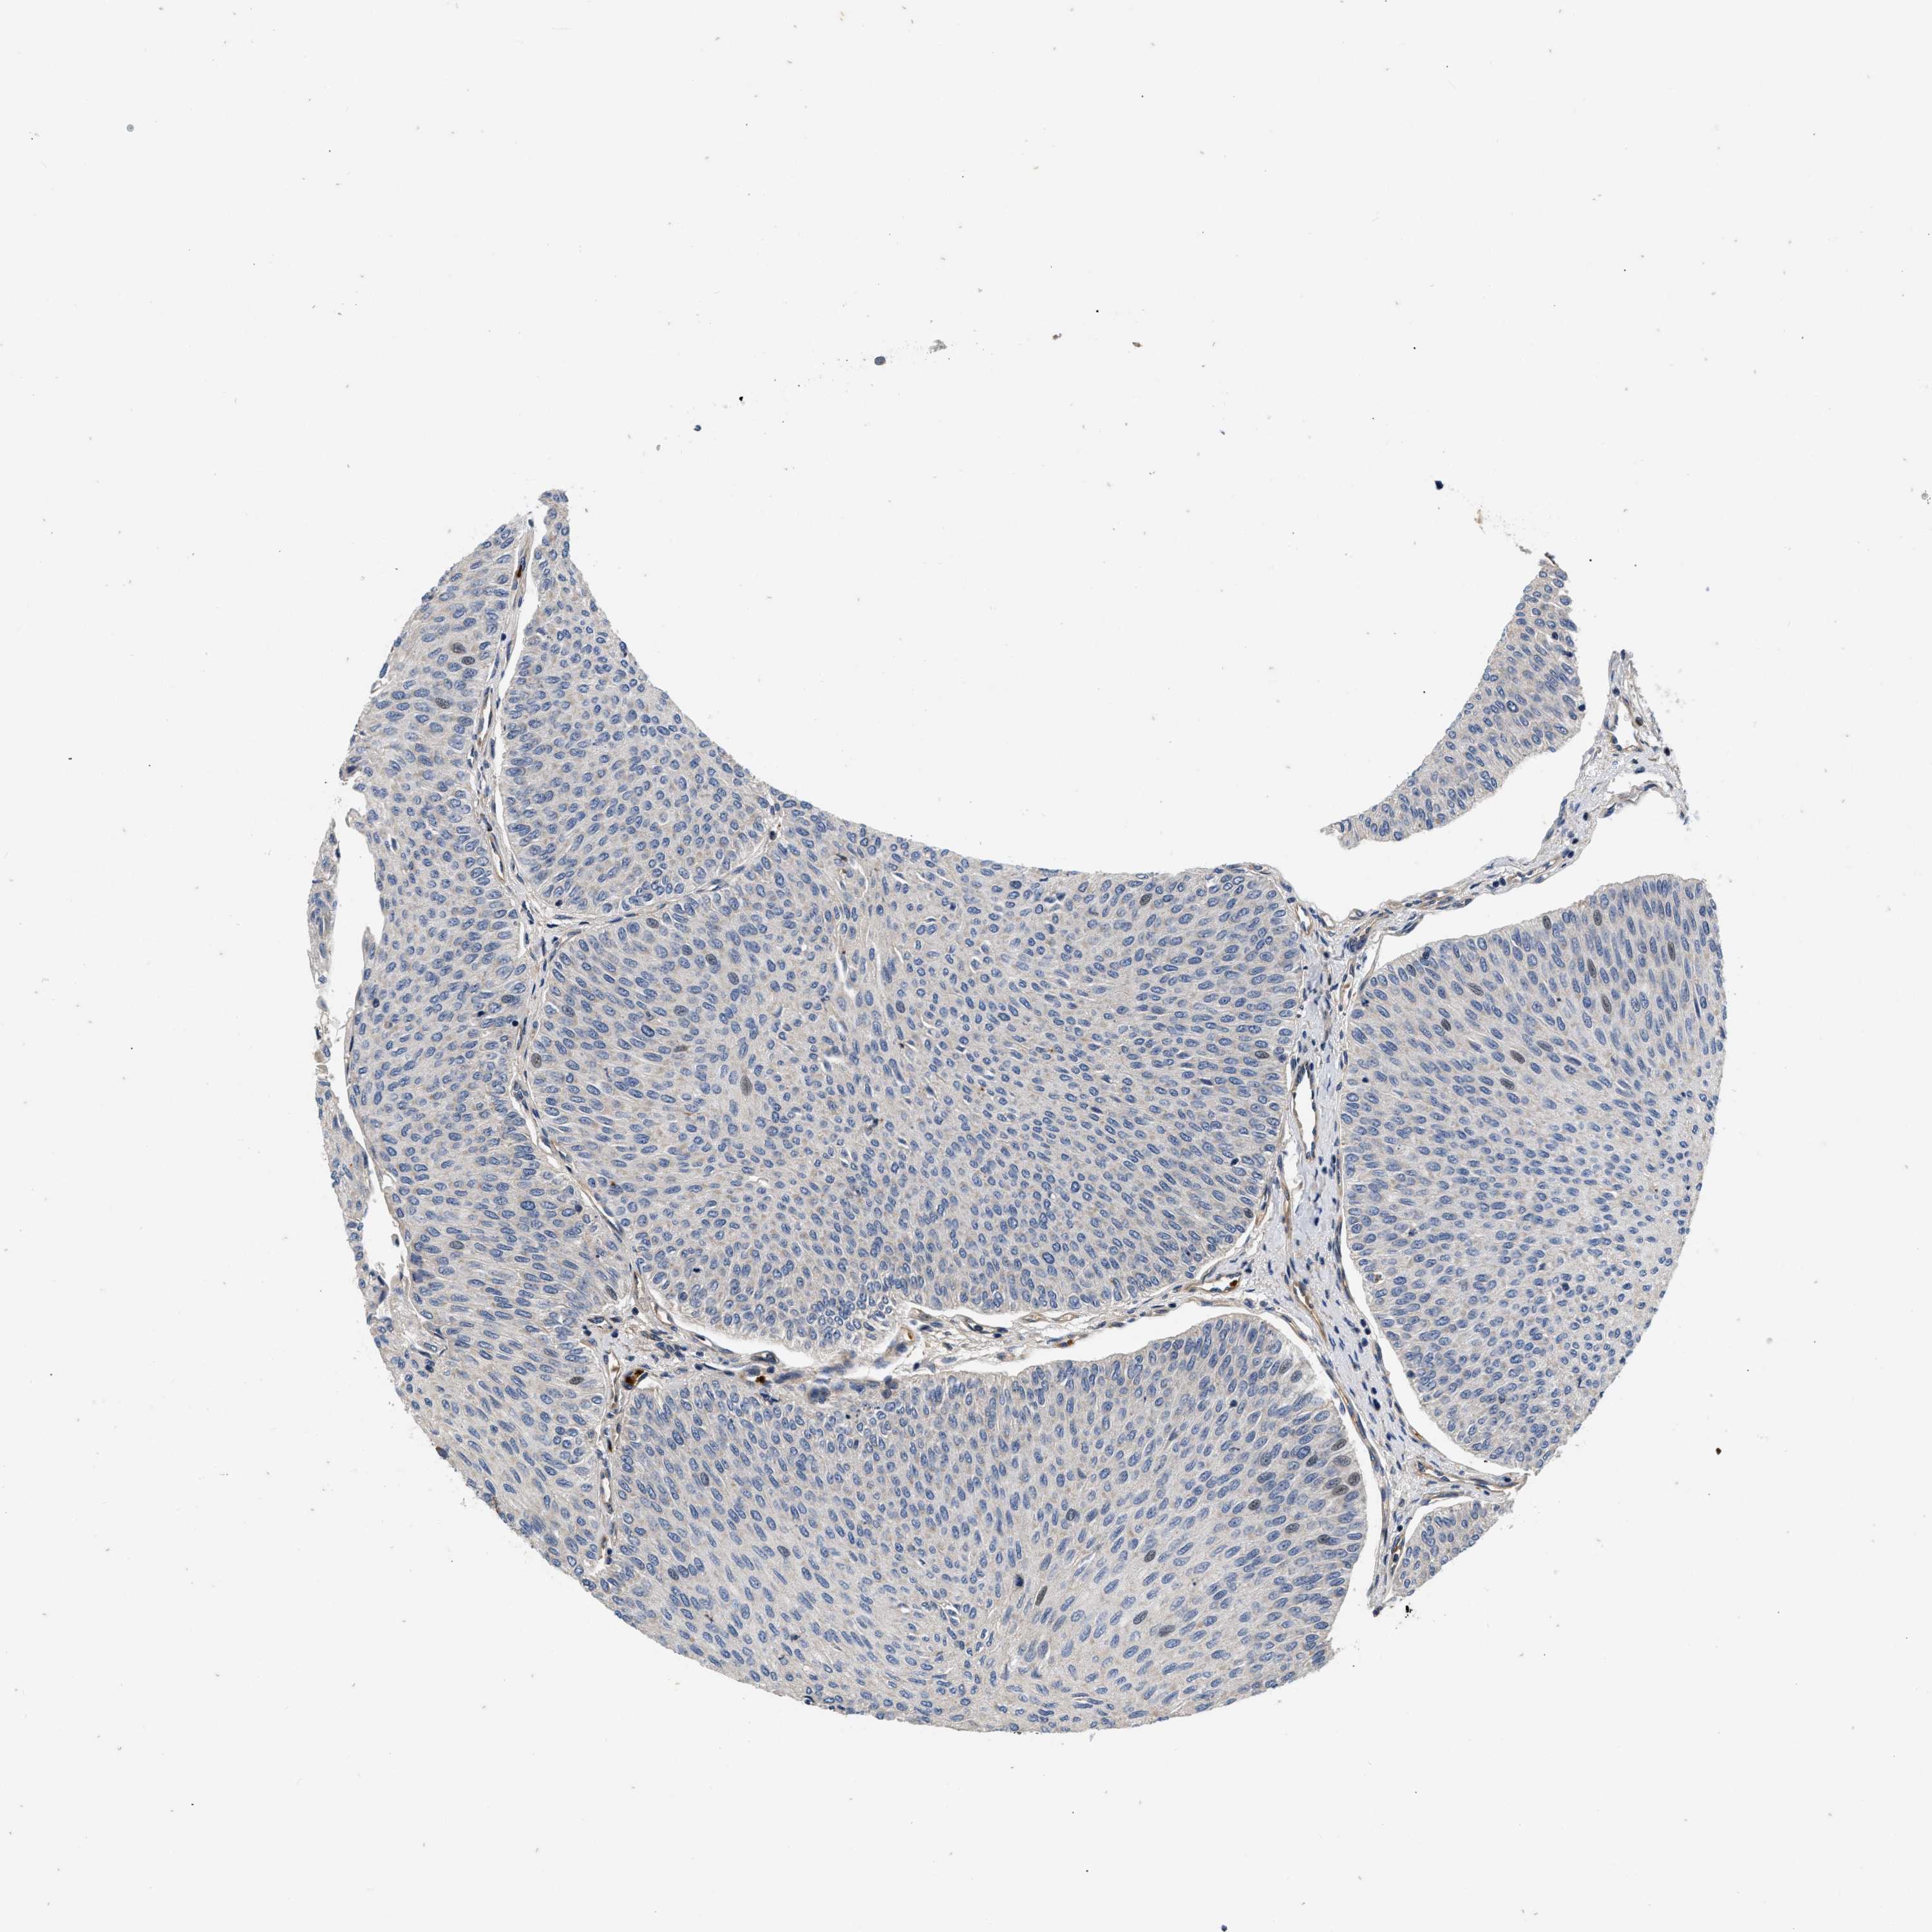

UROTHELIAL CANCER - Protein expressioni

A mouse-over function shows sample information and annotation data. Click on an image to view it in a full screen mode. Samples can be filtered based on level of antibody staining by selecting one or several of the following categories: high, medium, low and not detected. The assay and annotation is described here.

Antibody stainingi

Antibody staining in the annotated cell types in the current human tissue is reported as not detected, low, medium, or high, based on conventional immunohistochemistry profiling in selected tissues. This score is based on the combination of the staining intensity and fraction of stained cells.

Each image is clickable and will lead to virtual microscopy that enables deeper exploration of all samples and also displays staining intensity scores, fraction scores and subcellular localization as well as patient and tissue information for each sample.

Antibody HPA017909

Staining

Not detected

Negative

None

Urothelial carcinoma, Low grade